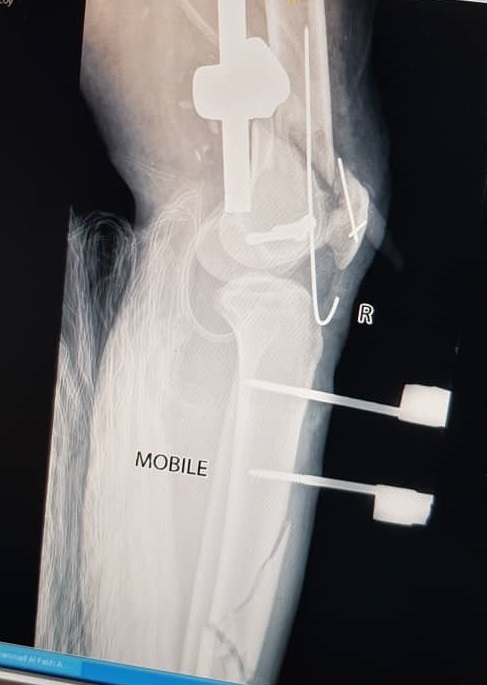

Initial management involved screw fixation of the femoral neck, wound debridement of the right thigh, and placement of an external fixator across the right knee (Figures 4 and 5), followed by a one-week course of intravenous cefuroxime. By January 2021, the right leg had become gangrenous and deemed nonviable. Right above-knee amputation (AKA) with adductor myodesis was performed, followed by intravenous cefuroxime for another week.